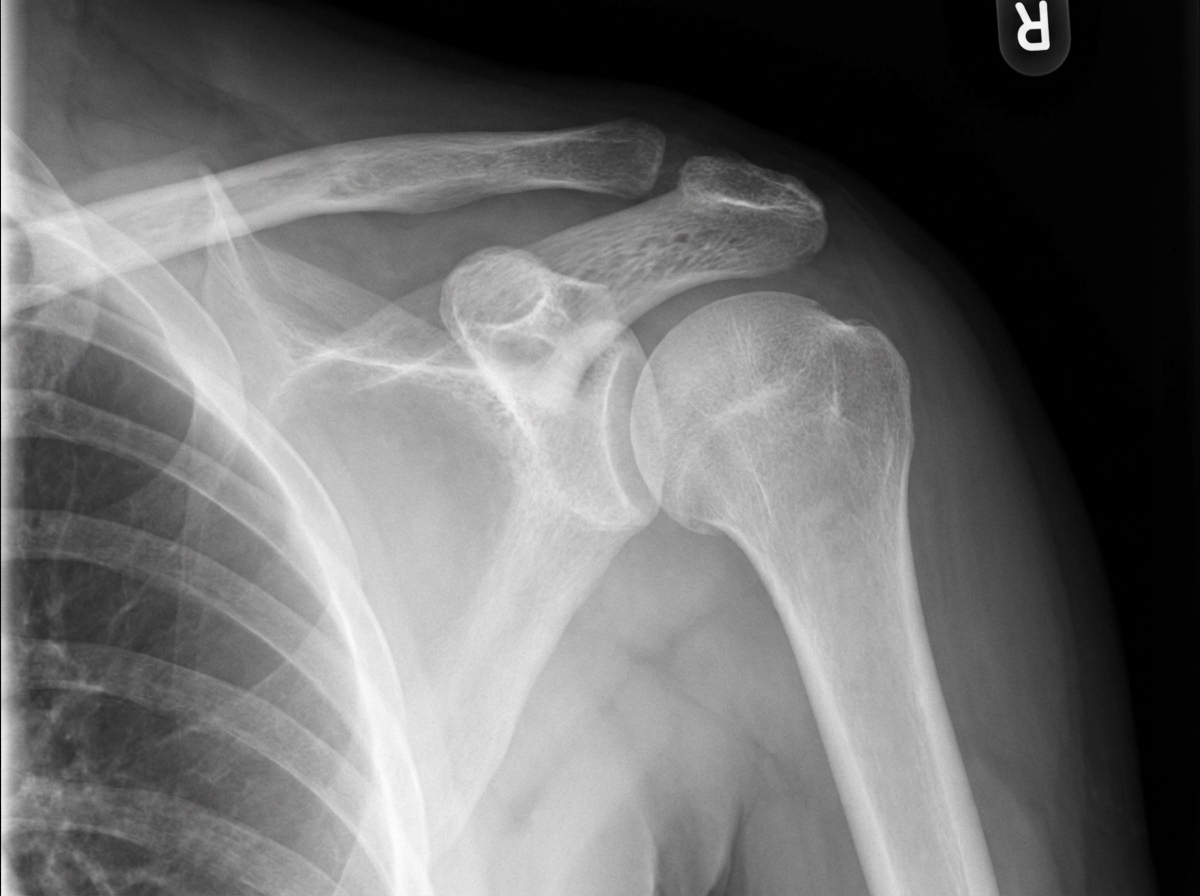

A student presents with a shoulder injury sustained while playing football. On comparing the symmetry of his two shoulders, a marked elevation of the distal end of the clavicle with respect to the acromion is noted on the injured side. X-ray examination reveals a grade III shoulder separation. Which ligament must be torn for this injury to have occurred?

Explanation: **Explanation:** The clinical presentation of a "marked elevation of the distal end of the clavicle" (Step-off deformity) following trauma is characteristic of an **Acromioclavicular (AC) joint dislocation**, commonly referred to as a "shoulder separation." **1. Why Coracoclavicular (CC) is correct:** The stability of the AC joint depends on two sets of ligaments: the **Acromioclavicular ligaments** (horizontal stability) and the **Coracoclavicular ligaments** (vertical stability). The CC ligament complex consists of the **Conoid** and **Trapezoid** ligaments. In a **Grade III injury**, both the AC and CC ligaments are completely ruptured. Because the CC ligaments normally anchor the clavicle down to the coracoid process, their tear allows the clavicle to be pulled superiorly by the trapezius muscle, resulting in the visible elevation noted in the question. **2. Why other options are incorrect:** * **Coracoacromial:** This ligament connects two parts of the same bone (scapula). It forms the coracoacromial arch but does not stabilize the clavicle. * **Costoclavicular:** This ligament anchors the medial (sternal) end of the clavicle to the first rib. It is not involved in distal shoulder separations. * **Superior glenohumeral:** This is a component of the shoulder joint capsule (glenohumeral joint) and provides stability against inferior translation of the humeral head, not the clavicle. **Clinical Pearls for NEET-PG:** * **Rockwood Classification:** Grade I (Sprain), Grade II (AC torn, CC intact), Grade III (Both AC and CC torn; 25-100% displacement). * **Piano Key Sign:** A classic physical exam finding where the elevated distal clavicle can be depressed but springs back up. * **Management:** Grade I-III are typically managed conservatively (sling/rehab), while Grade IV-VI usually require surgical intervention.